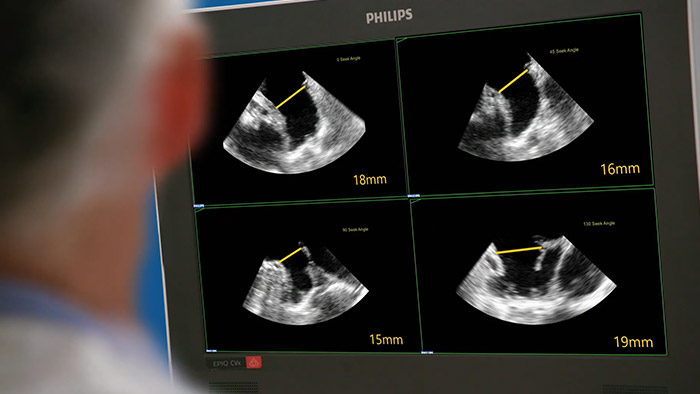

Snelle, eenvoudige en intuïtieve beoordeling van het linkerhartoor. De oplossing van Philips voor het linkerhartoor op EPIQ CVxi.